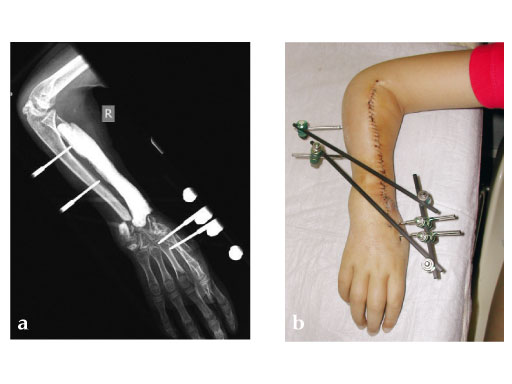

Fig 2ab: Resection of necrotic radius, temporary ExFix and pallacos spacer.

Fig 4ac: Postoperative.